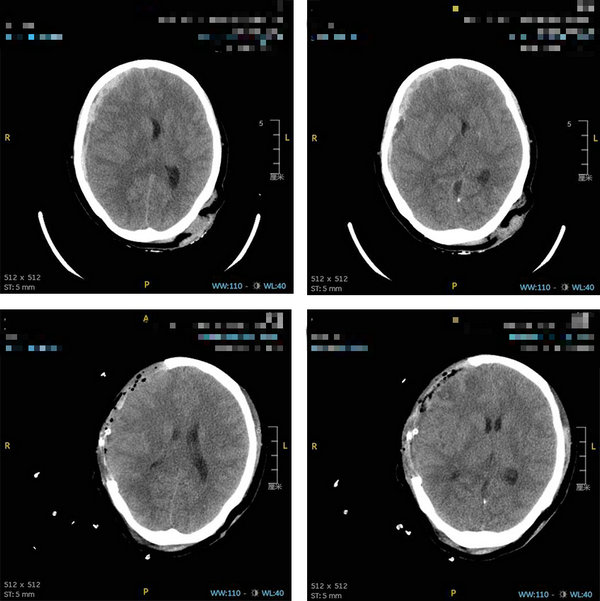

不久前的一天凌晨,孟女士(化名)骑共享单车时不慎摔倒被送到betway在线登陆急诊大厅,当时孟女士已经是神志不清并且处于深度昏迷状况。查头颅CT后发现患者右侧额颞顶硬膜下血肿并伴有脑疝,急诊科医生初步判断患者为重型闭合性颅脑损伤。

急诊科紧急联系了神经外副主任医师郑华煜。凌晨0点,孟女士被推进了手术室,郑华煜医生为病人进行了“开颅血肿清除、去骨瓣减压手术并进行颅内压检测”。在麻醉科和神经外科医生的配合下,手术用时3小时,患者颅内坏死的脑组织渐渐被清除掉。最终,在这场和死神的battle(战斗)里,医生又一次赢得了胜利。